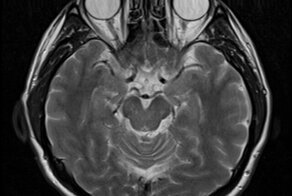

Джейнс пришёл к выводу, что разум наших предков был «двухпалатным», что было обусловлено двухполушарным устройством головного мозга. В привычных ситуациях человек руководствовался привычками и инстинктами, а когда возникала проблема, требующая нестандартного разрешения, то подключалась та самая «вторая палата», которая находится в правом полушарии. По представлениям Джейнса, полушария человеческого мозга — это вообще два отдельных органа. Левое полушарие отвечает за выполнение повседневных задач, правое — за память и решение «особых» проблем.